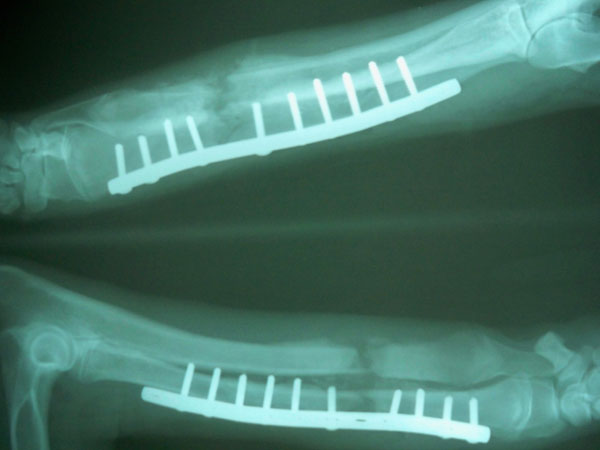

Χειρουργήθηκε και είναι απολύτως φυσιολογικό. Οι ακτινογραφίες είναι πριν και μετά το χειρουργείο.

Τσοπανόσκυλο 7 μηνών με 2 εβδομάδων τέλειο κάταγμα κάτω τρίτου μεσότητας διάφυσης αριστερής κερκίδας και ωλένης.

Στις 5/1209 πραγματοποιήθηκε ορθοπεδικό χειρουργείο. Η προνάρκωση του ζώου έγινε με ξυλαζίνη και ατροπίνη, η εγκατάσταση

της αναισθησίας με πεντοθάλη 2,5 % και διατήρηση της αναισθησίας με εισπνεύσιμο αναισθητικό ( ισοφλουράνιο).

Διεγχειρητικά χορηγήθηκε Tolfendine 3ml, Dalacin 10mg/kg και Marbocyl 3ml.

Αποκατάσταση του κατάγματος έγινε με τοποθέτηση μεταλλικής πλάκας στην έσω επιφάνεια της κερκίδας με 6 κοχλίες στο κεντρικό

τμήμα και 4 κοχλίες στο περιφερικό τμήμα. Μετεγχειρητικά χορηγήθηκε για 5 ημέρες Dalacin 10mg/kg BID.